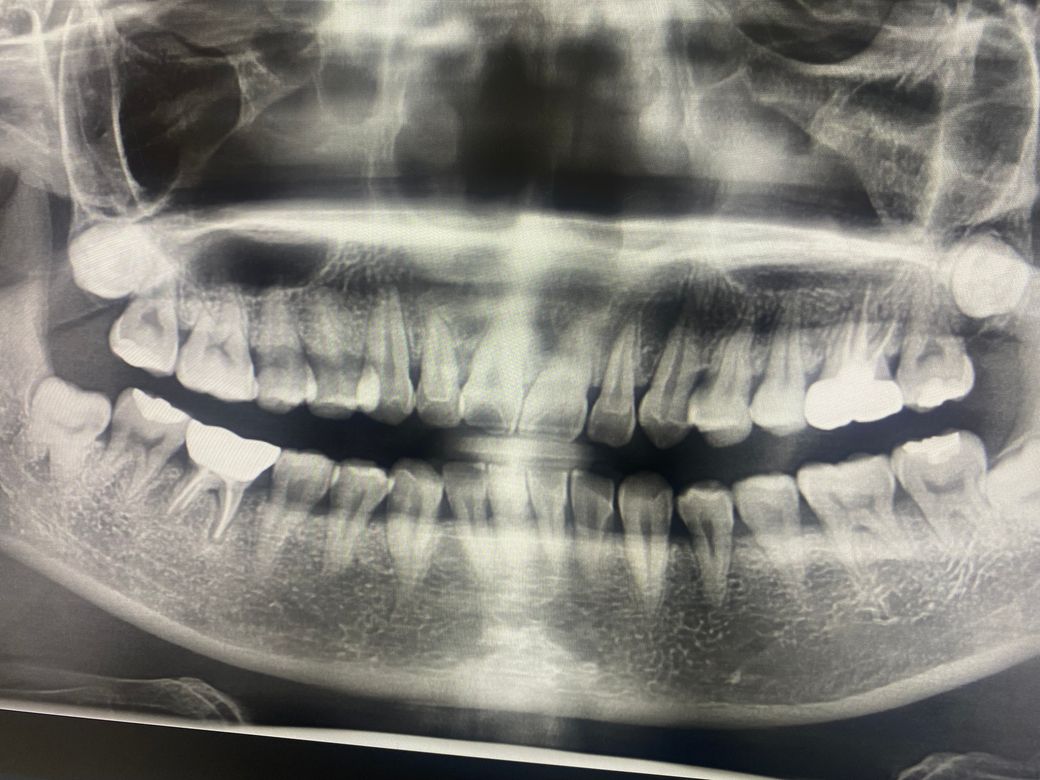

엑스레이상으론 잇몸에 나오는 염증은 안 보이나요??????

크라운 한 어금니에 잇몸에 고름이 나와 검사했는데요

엑스레이 상으로 보면 신경치료를 한 주변으로 치주인대가 늘어나서 염증이 잇는것처럼 보입니다.

엑스레이 상에서 염증이나 뼈가 녹은 것들이 관찰됩니다. 염증이 생기면 뼈가 녹는 것 입니다.

염증이 있는 부위는 방사선상에 어두운 부위로 보이게 됩니다.

사진으로 봤을 경우 큰 병소가 보이진 않지만 오른쪽아래 어금니 뿌리에 방사선 음영이 보이고 있습니다.

정확한 확인을 위해서는 치과에서 진료를 받아 보는것이 좋습니다.

염증조직은 엑스레이상 잘 안보일수도 있으나 염증이 있으면 잇몸뼈가 녹습니다 잇몸뼈 녹을 걸 보고 염증이 있다고 할 수 있습니다